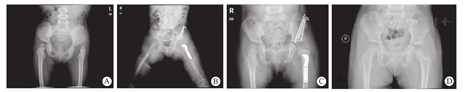

所有患儿术前拍摄骨盆正位片,髋关节三维骨盆CT重建影像,术后按照Kalamchi-MacEwen分型方法判断是否发生AVN并进行分级评估[10](图1)。功能结果采用McKay评分分析。由三位医生记录相关数据。所有测量结果定量参数取其均值,定性参数取多数认同者。

根据McKay临床分期:优秀33髋(73.3%),良好7髋(15.6%),一般4髋(8.9%),差1髋(2.2%)。在1组中,优秀21髋(75.0%),良好4髋(14.3%),一般3髋(10.7%),在2组中,优秀12髋(70.6%),良好3髋(17.6%),一般1髋(5.9%),差1髋(5.9%)。两组之间差异并无统计学意义(P=0.944)。典型病例见图2,临床数据及分析见表1。